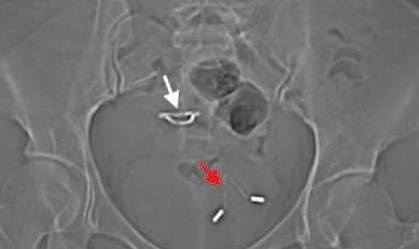

Sau khi nghe nữ bệnh nhân mô tả các triệu chứng, bác sĩ đã cho chụp X-quang và phát hiện có một chiếc vòng tránh thai nằm ở vùng bàng quang.

| Ảnh chụp X-quang cho thấy chiếc vòng nằm trong bàng quang của nữ bệnh nhân. Ảnh: Live Sience. |

"Vòng tránh thai đi vào bàng quang gây nên các triệu chứng của bệnh tiết niệu là điều hiếm khi xảy ra", bác sĩ tại bệnh viện Cát Lâm, Trung Quốc nhấn mạnh.